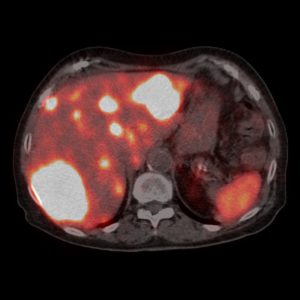

PET/CT vyšetrenie s 18F-cholínom

Diagnostika hepatocelulárneho karcinómu a adenómu paratyreoidey